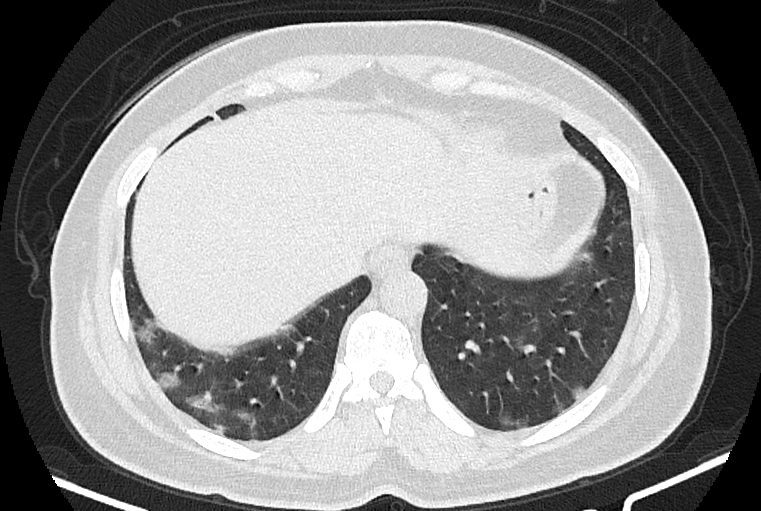

در HRCT از ريه ها(اسپيرال ، مولتي ديتکتور 16، مقاطع اگزيال با ضخامت 1mm بدون فاصله ) ، بدون كنتراست تزريقي :

-Ground glass opacities Patchy پراکنده در ريه ها مشهود است که مطرح کننده Viral pneumonia مي باشد . ( با درگيري 20 درصد حجم ريه )

-کلسیفیکاسیون دیواره آئورت و عروق کرونر ، تغییرات DJD در ستون فقرات ونشانه های CABG مشهود است .

نتیجه : Highly suggestive of COVID-19